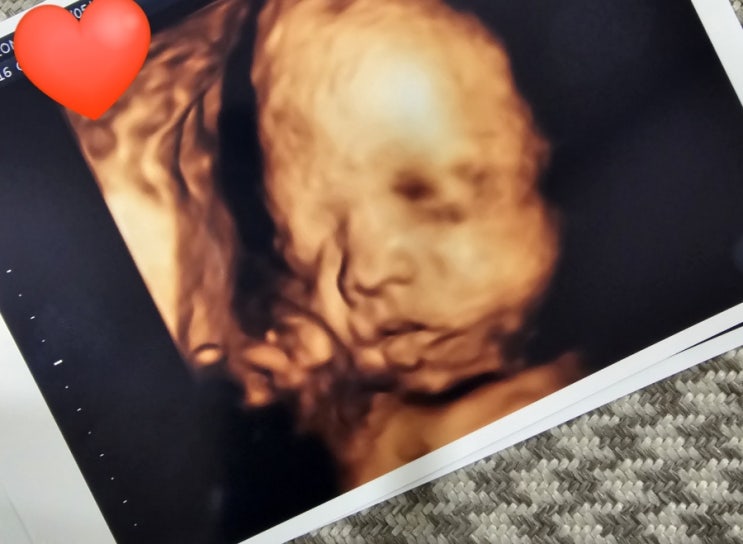

둘째)임신27주 아들 입체초음파,철분부족 약바꾸기

입체초음파 초코없이도 잘 보였어 둘째)임신27주 아들 입체초음파보고 왔는데 첫째랑 닮았다 하는 식구들 ...